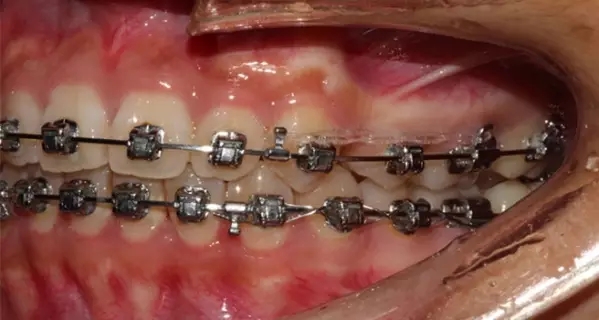

Damon 病例分享:安氏 II 類二分類露齦笑的矯治(董一磊)